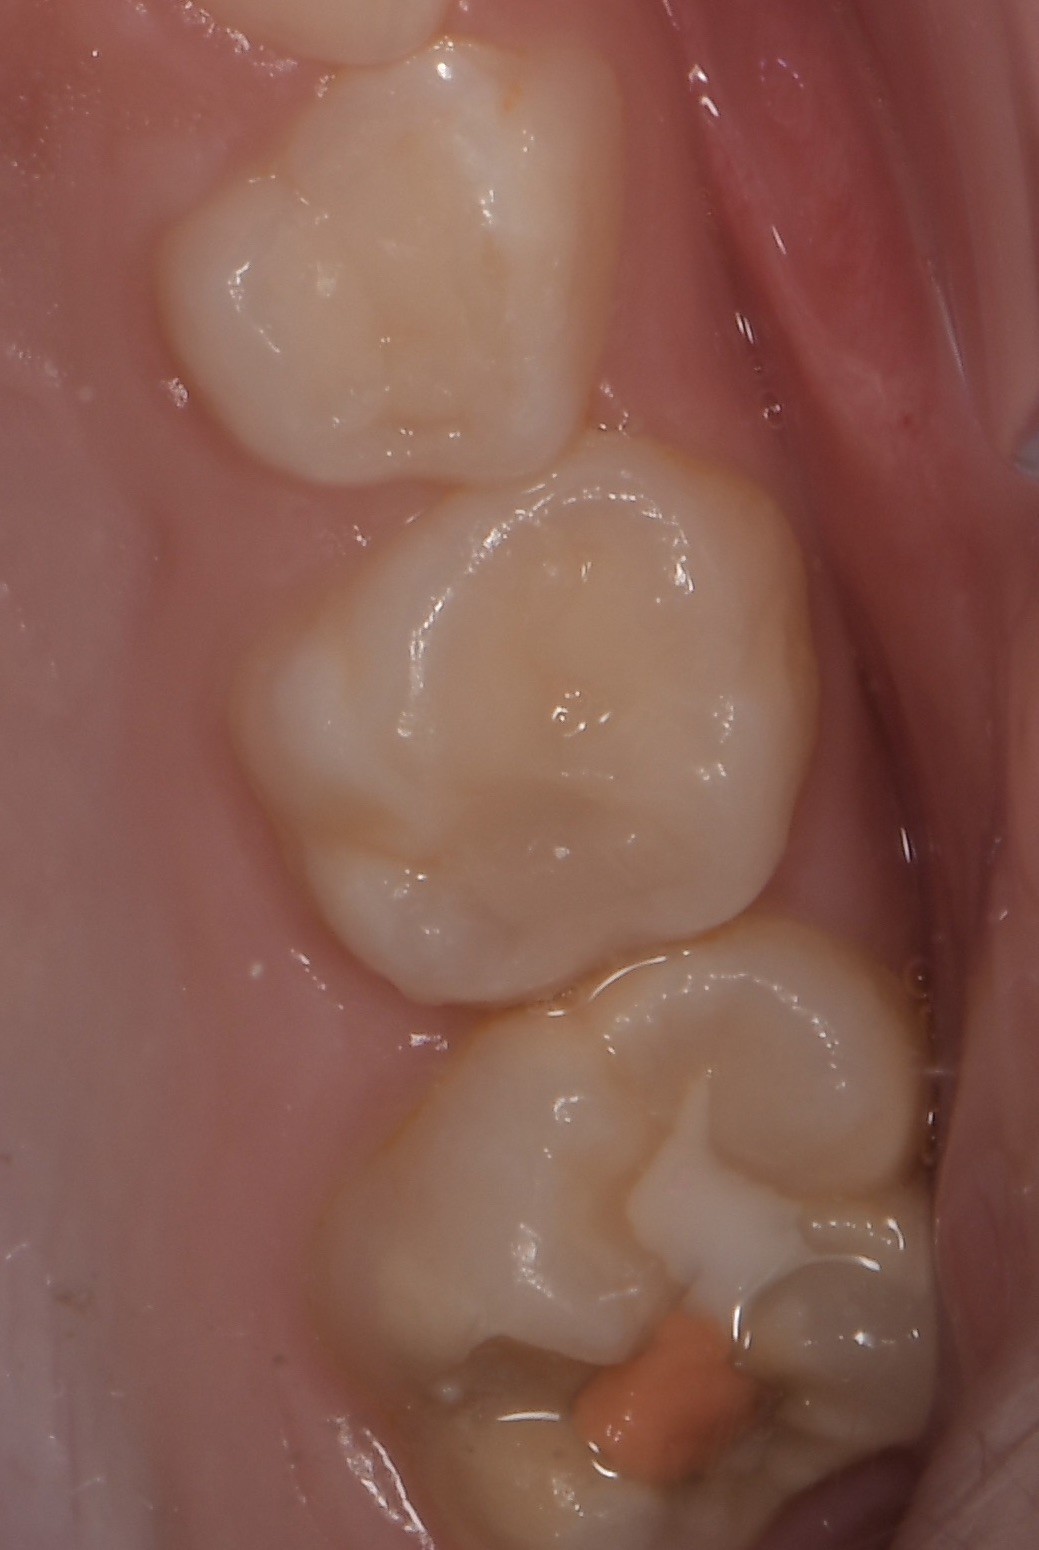

Le congrès de l’EAPD (Académie Européenne d’Odontologie Pédiatrique) a défini des critères de diagnostic en 2003. A savoir des opacités délimités, des fractures post-éruptives, des restaurations atypiques ainsi que que des extractions des molaires. (3) Le diagnostic différentiel doit surtout s’établir entre des amélogénèses imparfaites et des hypominéralisations d’origine traumatique pour les dents antérieures. Cliniquement, les dents vont présenter des colorations blanches ou brunes opaques sur une partie ou sur toute la surface de la dent (Figures 1-2-3-4).

Cette atteinte peut être soit légère (émail blanc, opaque), soit modérée (coloration jaune, brune, surface crayeuse et effondrement postéruptif de l’email ou PEB) ou enfin sévère (atteintes associées à des pertes de substances importantes). De plus, l’intégrité de la dent peut être aussi touchée. Plus la MIH est sévère et plus le manque d’émail sera important donc plus les sensibilités/douleurs seront importantes aussi. Cette sévérité varie en fonction des personnes, mais également au sein des dents d’un même individu : on parle d’atteinte asymétrique. Toutes les dents ne sont pas toutes touchées de la même façon, et ne nécessiteront donc, pas les mêmes types de soin.

Pour les secteurs postérieurs, en fonction du délabrement tissulaire (PEB ou consécutif à une atteinte carieuse), on optera pour des restaurations directes en composite (Figures 11-12).

ou indirectes de type onlay en céramique (Figures 13-14-15).

Figure 3-4 : Molaires atteintes de MIH (HSPM + MIH pour la figure 3)

Figures 13-14-15 : TraitemEnt postérieur par onlay céramique.